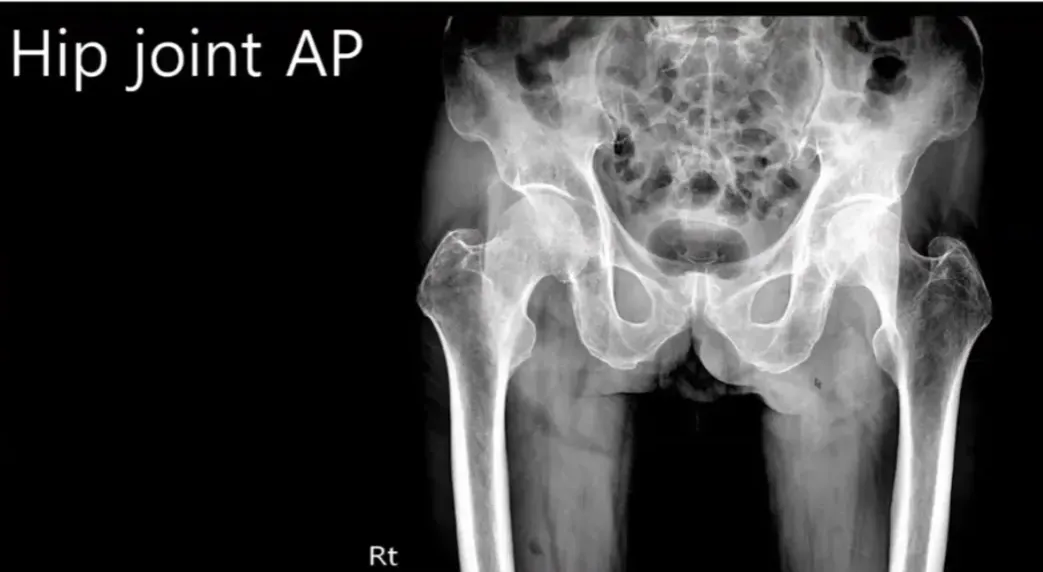

B. 힙조인트 판독 및 ABC 접근법

힙조인트 판독 시 어댓거시를 확인하고, 이를 위해 레서트롯 센터를 관찰해야 한다. 45

레서트롯 센터가 두드러지면 발끝의 외회전을 나타내며, 이는 올바른 X-Ray가 아님을 의미한다. 49

올바른 X-Ray는 레서트롯 센터가 조금 튀어나오고, 이를 통해 힙조인트의 명확한 모습을 확인할 수 있다. 53

힙조인트의 얼라인먼트 확인을 위해 쉔톤 라인을 그리고, 이는 Firmor와 Helvix 간의 문제를 나타낼 수 있다. 56

피머 넥 프랙처는 피머의 세 가지 영역(서브캐피탈, 스트레스 서비칼, 바지 서비칼)에서 발생하는 골절을 지칭하며, 이들 영역의 이해가 중요하다. 66